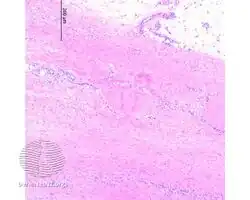

Additional images

-

Eosinophilic fasciitis/pathology -

Eosinophilic fasciitis/pathology